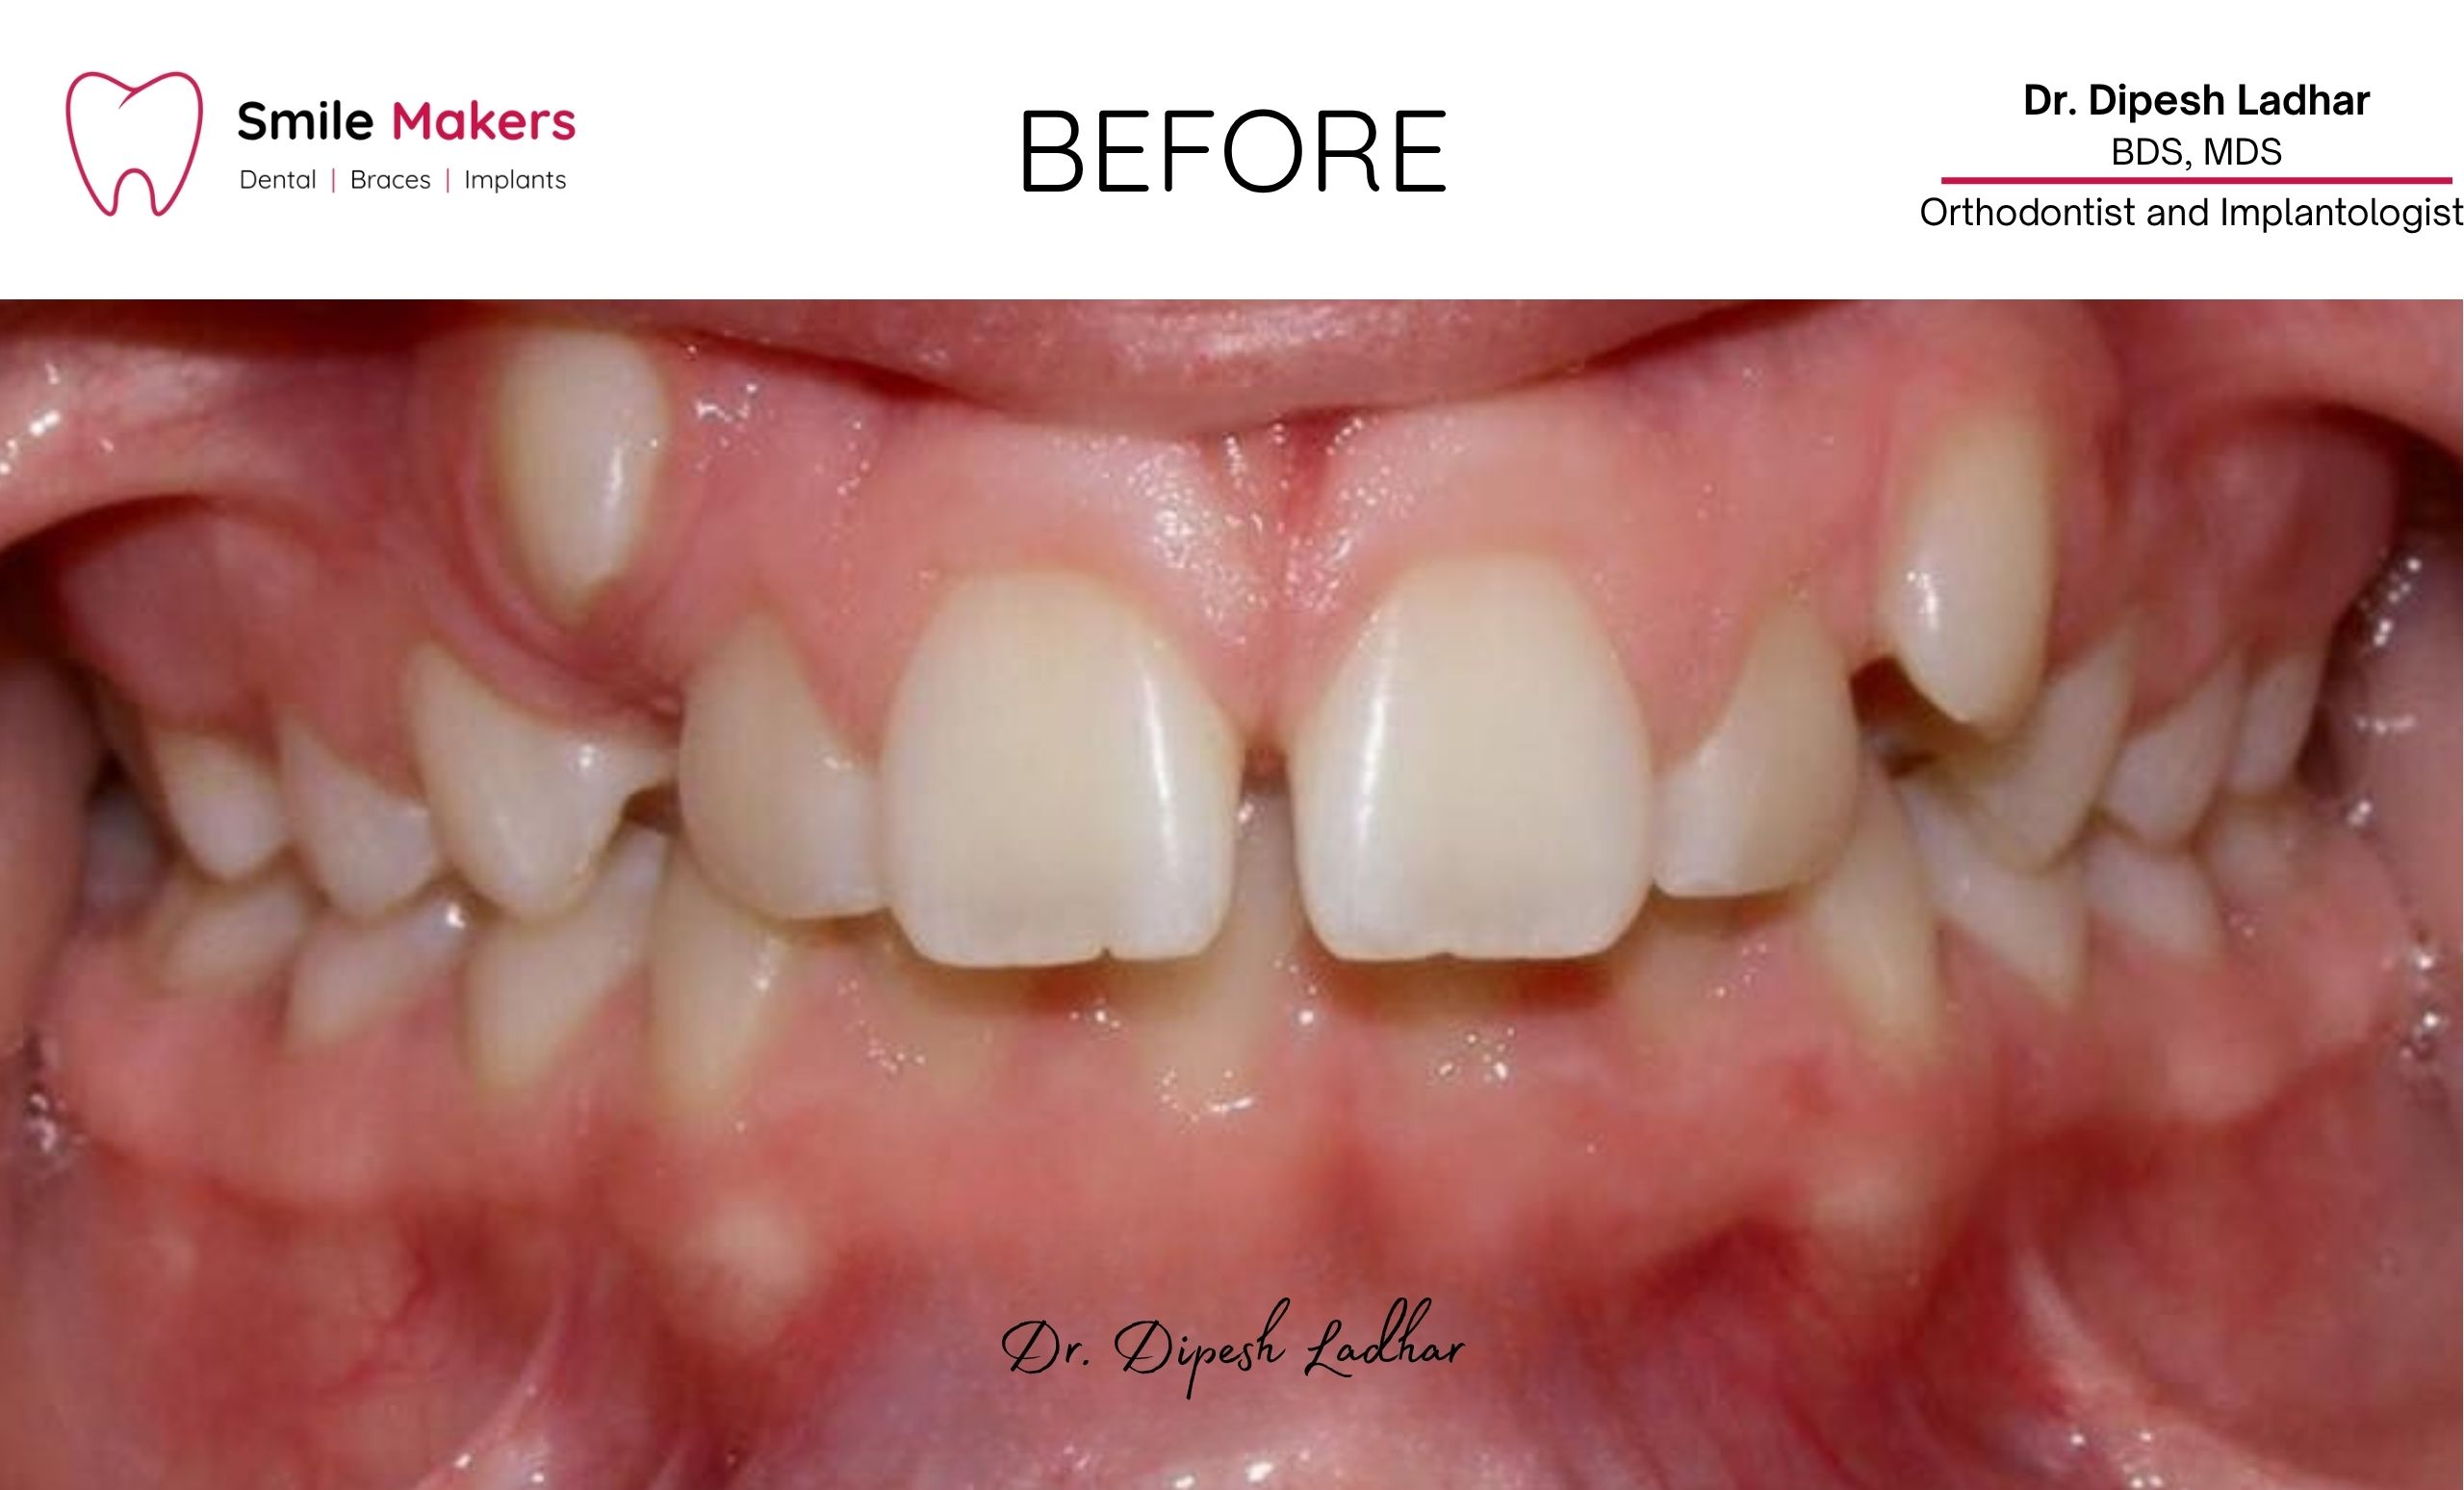

Smile Transformations